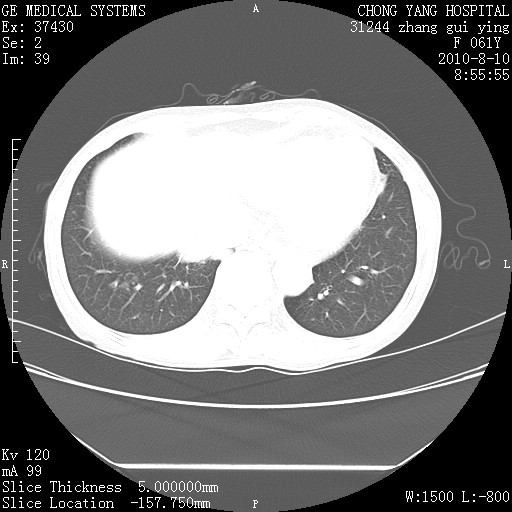

标题: CT28314:F61Y胸部增强,发热咳嗽一周入院,后面的为一周前平 [打印本页]

标题: CT28314:F61Y胸部增强,发热咳嗽一周入院,后面的为一周前平

1、支持考虑右侧中央型肺癌伴右肺中叶节段性不张及下叶支气管黏液痰栓    2、左肺上叶舌段感染。

确切的说:1:右肺下叶中心型肺癌侵及中叶支气管并中叶不张,纵膈淋巴结转移。2:左肺舌叶炎症。3:右侧胸腔少量积液

块影平扫32hu,动静脉期62-70hu.

右肺下叶内基底段近膈不规则肿块,考虑右肺下叶周围型肺癌可能性大。